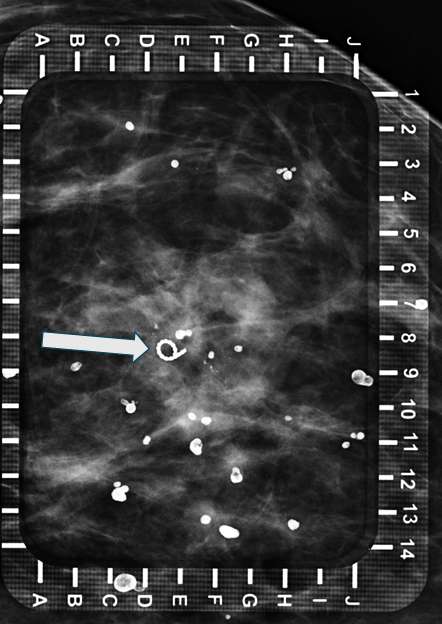

Technologist obtains image to confirm location of needle over targeted lesion (within 0.5 cm) (Figure 2).

Procedure Mammographically Guided Wire Localizations Figure 2

Figure 2: Same patient as Figure 1, still in CC view. A hollow needle has been placed targeting the residual calcifications and microclip. Note that the needle appears as a perfect circle due to perpendicular approach.